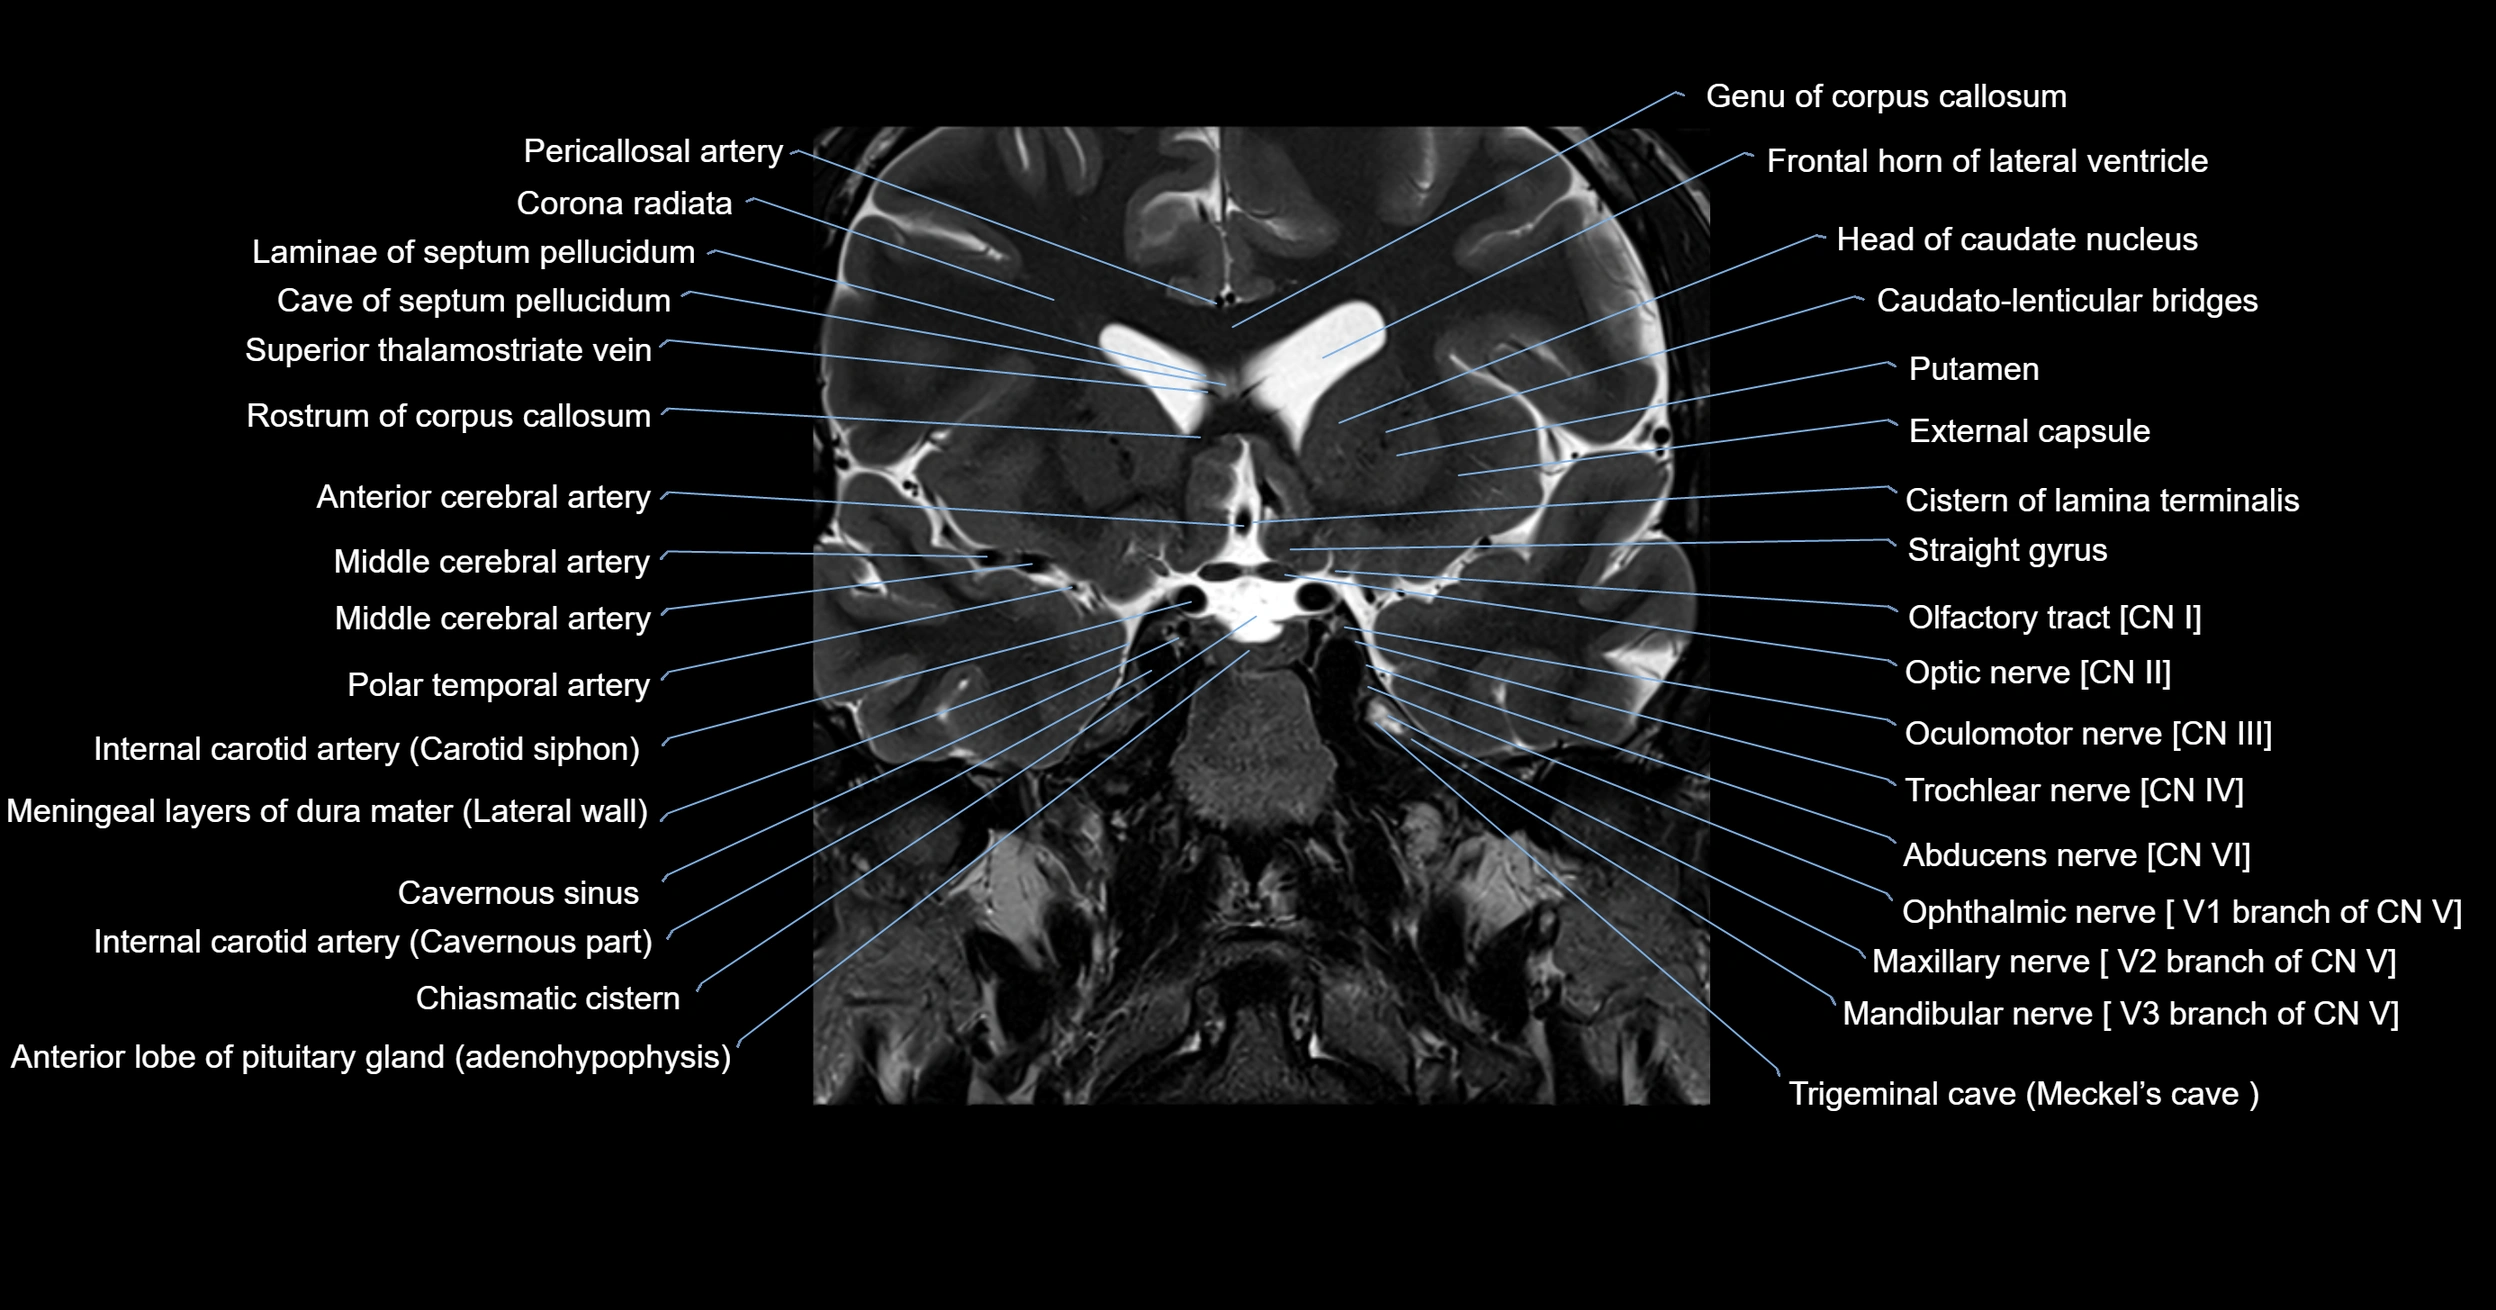

MRI images